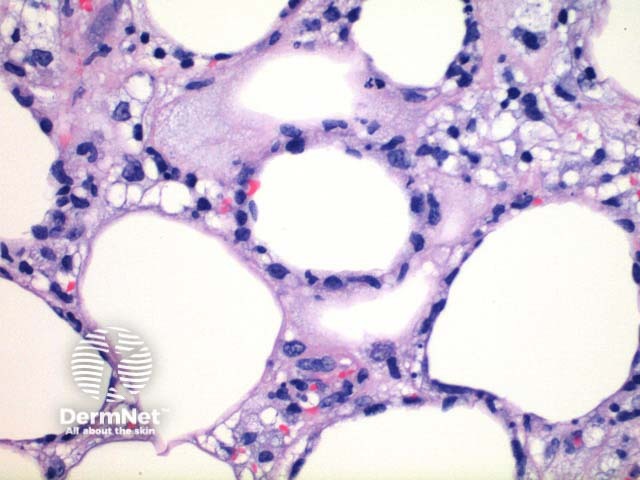

Scanning power view demonstrates lobular panniculitis (Figure 1). Relatively little dermal or epidermal involvement is seen (Figure 2). A dense infiltrate is seen predominantly within the fat lobules while some spillover into the septal panniculus may be seen (Figure 3). Germinal centre formation is rare. The infiltrate is predominantly lymphocytic with variable numbers of histiocytes engulfing nuclear debris (bean bag cells) and lipid (lipophages) (Figures 4 and 5). The lymphocytes demonstrate nuclear atypia and can be seen to characteristically rim the adipocytes (Figure 6).

Figure 4